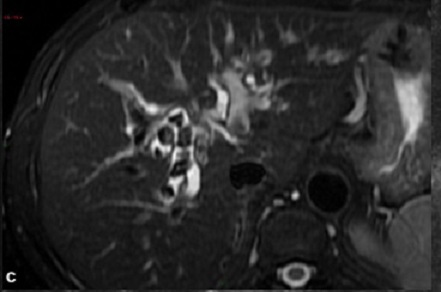

Image IRM , cholangio IRM et

ERCP : Stenose multifocales avec

dilatations segmentaire des voies biliaires

intra et extrahepatique , image de pseudo-diverticule

biliaire , bord du voie biliaire est

irregulier ou bien image de distortion des voies

biliaire en cas de cirrhose du foie .

Aspect de fibrose

stenosant multifocale avec dilatation

segmentaire systematise de voie biliaire

intrahepatique du foie droit ( cholangite

sclerosant primitive ) . Image radiologique

IRM en coupe coronal , pondere sur T2 |

|

Image

cholangio IRM des voies biliaires du foie

droit d'une cholangite sclerosant primitive

. Aspect de dilatation discontinue par des

segment stenose fibrosant de voie biliaire

intra et extrahepatique ( fleche rouge ) |

Cholangite sclerosant

primitive du foie avec image de fibrose

stenosant systematise des voie biliaire

intrahepatique . Le canal biliaire est tres

petit , bord irregulie , discontinue par

quelque portion dilate en vue tres nette sur

ce coupe , les voie biliaire peripherique

sont dilatees ( image typique de CSP )

. Le bas du canal choledoque et une partie

du canal hepatique sont en stenose . Image

radiologique cholangio IRM de voie biliaire |

Image de

deorganisation et irregularite des voies

biliaires intrahepatique ( VBIH ) en vue

tres nette (CSP) . Dilatation moniliforme (

fleche blanche ) et dilatation de voie

biliaire peripherique . Image de CSP en

cholangio-IRM coupe frontale . |